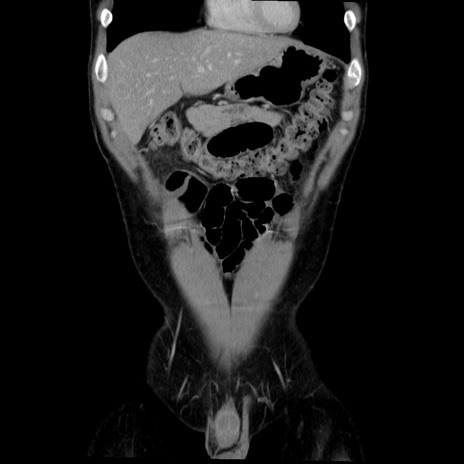

症例36(冠状断像)

【症例】20歳代 男性

【主訴】心窩部痛

【現病歴】今朝より上腹部痛あり。一旦軽快していたが再度出現したため救急要請。昨日夕に白身の魚を含む刺身を食べた。

【身体所見】BP 136/89mmHg、HR 74/min、BT 37.0℃、腹部:膨満、軟、心窩部に圧痛あり。反跳痛なし、筋性防御なし、腸雑音やや亢進あり。

【データ】WBC 17700、CRP 0.48